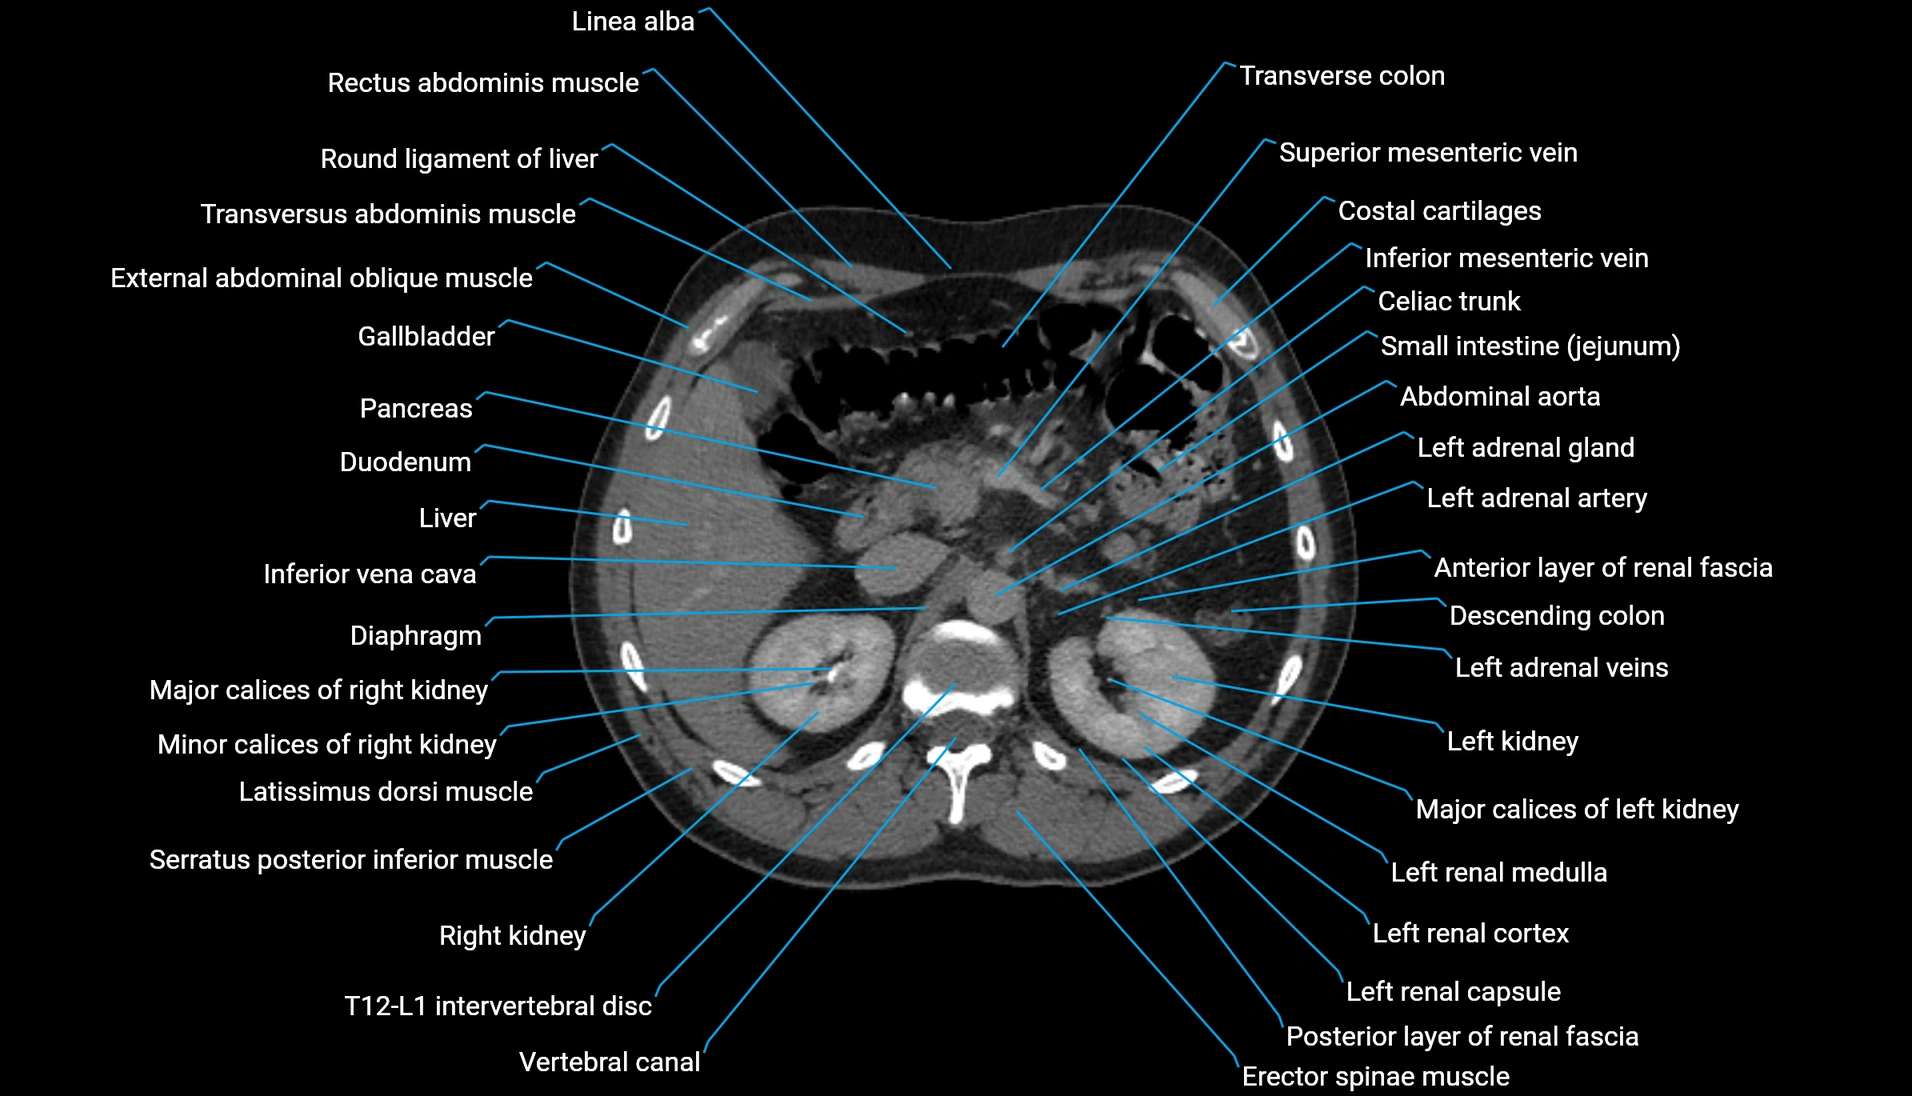

CT Appearance

Non-contrast CT:

-

Demonstrates cortical bone of acetabular rim in excellent detail

Detects fractures, dysplasia, retroversion, or bony overcoverage (pincer impingement)

3D reconstructions used in preoperative hip surgery planning

CT VRT 3D image

CT image